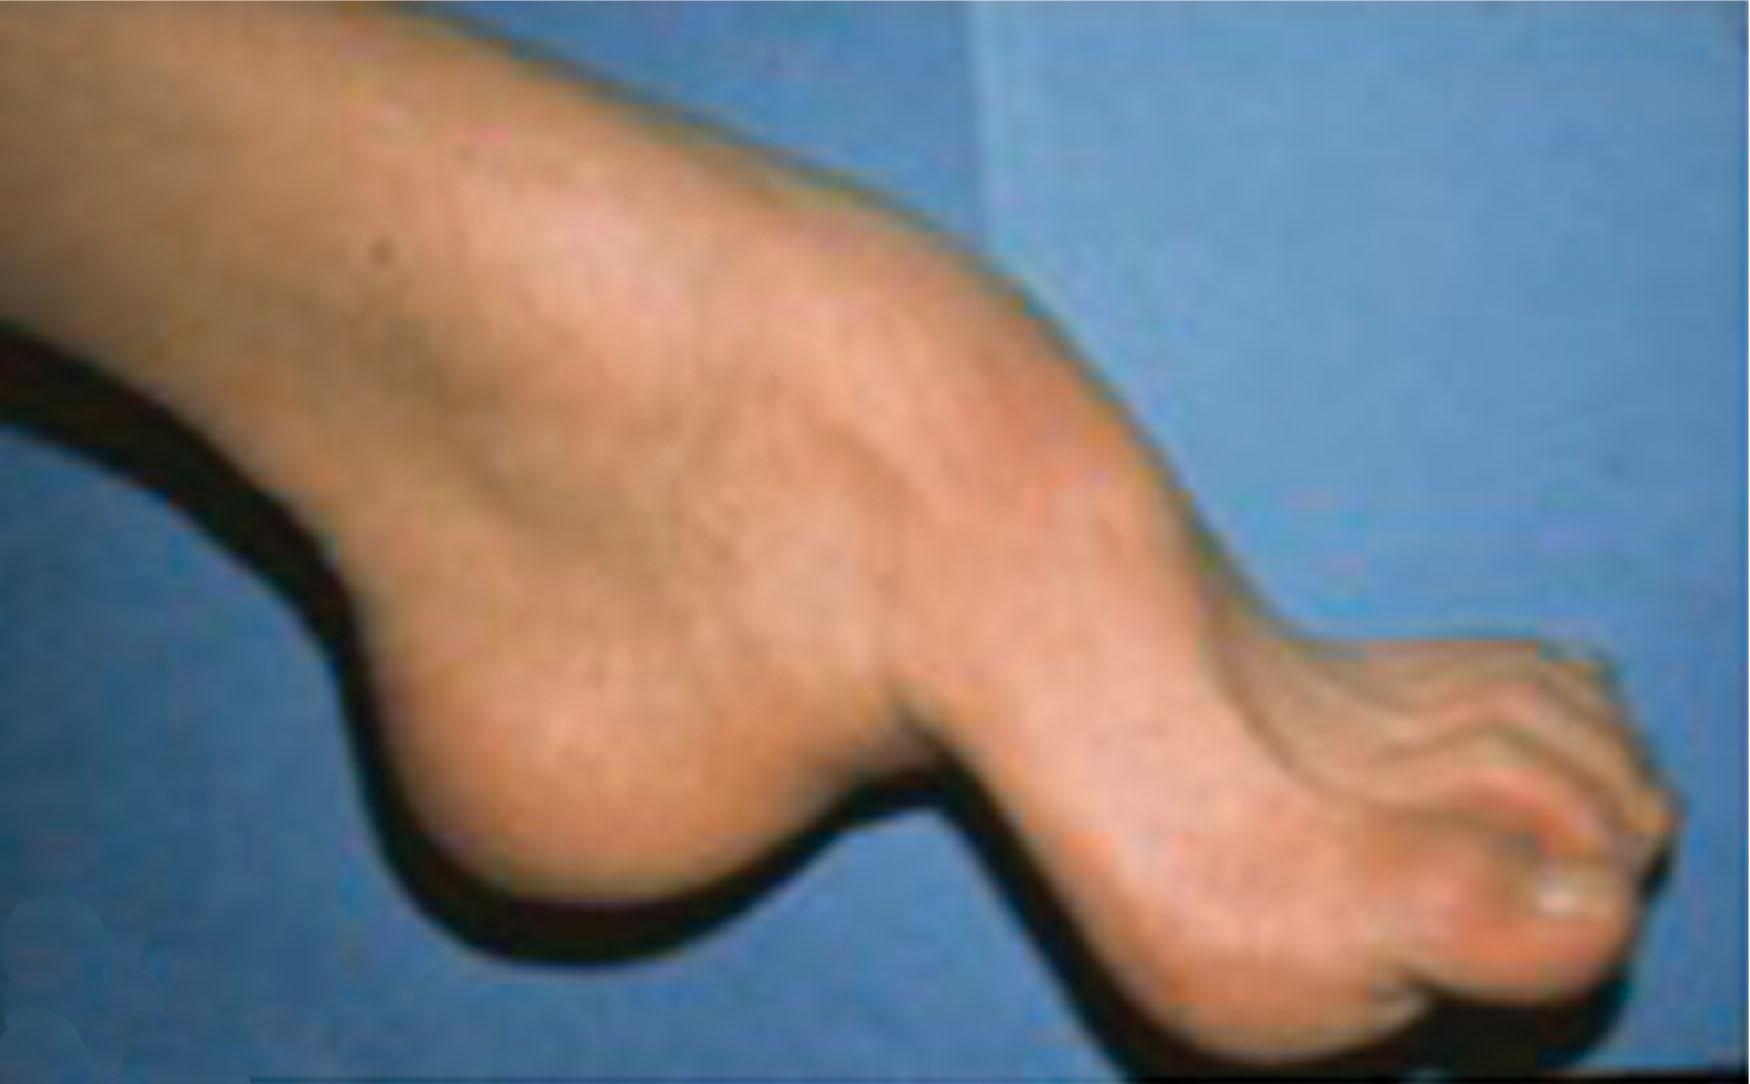

A claw toe deformity usually involves multiple toes and often both feet ( Figs. 9-24 and 9-25 ). The deformity may be either rigid or flexible. It is often associated with a cavus foot, with or without a contracted Achilles tendon. Claw toes are often made worse because the patient cannot find adequate shoes, and a painful bursa develops over the PIP joint. As the claw toe deformity becomes more rigid, the toes strike the top of the shoe, and the metatarsal heads are forced plantarward. As the toes subluxate dorsally, the plantar fat pad is pulled distally, and the metatarsal heads become more prominent on the plantar aspect of the foot. This deformity can result in the development of painful plantar callosities, which can ulcerate in severe cases, particularly if sensation of the foot is impaired.

Fig. 9-24, Lateral view of foot with claw toe deformities with an underlying diagnosis of Charcot-Marie-Tooth disease.